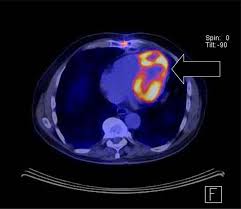

However, some researchers [15, 32] have shown that well-trained models do not perform well when the testing images come from a different statistical distribution from the training images. This domain shift problem is common in real-world medical diagnosis since medical images at various steps of the clinical procedure are often obtained with different physical properties [6]. For instance, Magnetic Resonance Imaging (MRI) and Computed Tomography (CT) play complementary roles in cardiac disease diagnosis while also exhibiting different appearances (See Fig. 1). That difference post challenges for analyzing the MRI and CT images in clinical diagnosis.

We consider two benchmark datasets for model performance comparison, including Multi-Modality Whole Heart Segmentation (MM-WHS) Challenge dataset [41] and Multi-Sequence Cardiac MR Segmentation (MS-CMRSeg) Challenge dataset [40]

MS-CMRSeg Dataset contains 35 labeled bSSFP CMR 3D images and 45 labeled 3D LGE-MRI images, which are also not paired. Each image is cropped to a size of 192192.